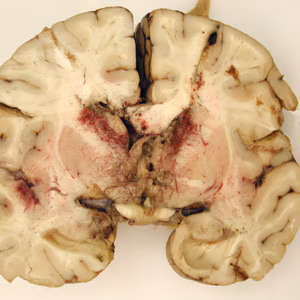

Gross pathology images in free-living amebic infections.

Naegleria fowleri: PAM is characterized by severe CNS dysfunction with rapid degeneration caused by hemorrhagic-necrotizing meningoencephalitis. Unlike GAE, the onset of PAM symptoms occurs quickly following infection (1-9 days; median 5 days after swimming or other nasal exposure to Naegleria-containing water). Symptoms are similar to bacterial meningitis, for which it is often mistaken, with deteriorating neurological function and complications. The case fatality rate is extremely high.